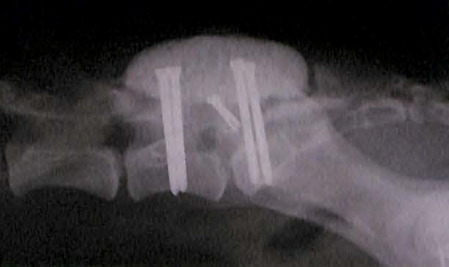

外科手術は下図ようにL7-仙椎の背側の骨を削り、馬尾神経にかかる圧を逃すための隙間をつくります。さらに、背骨の動きに伴う病気であることや、術後の不安定性を解消する目的でスクリューや医療用セメントを用いて固定をします。これにより動きに伴う神経の圧迫が解消され、症状の改善が認められます。